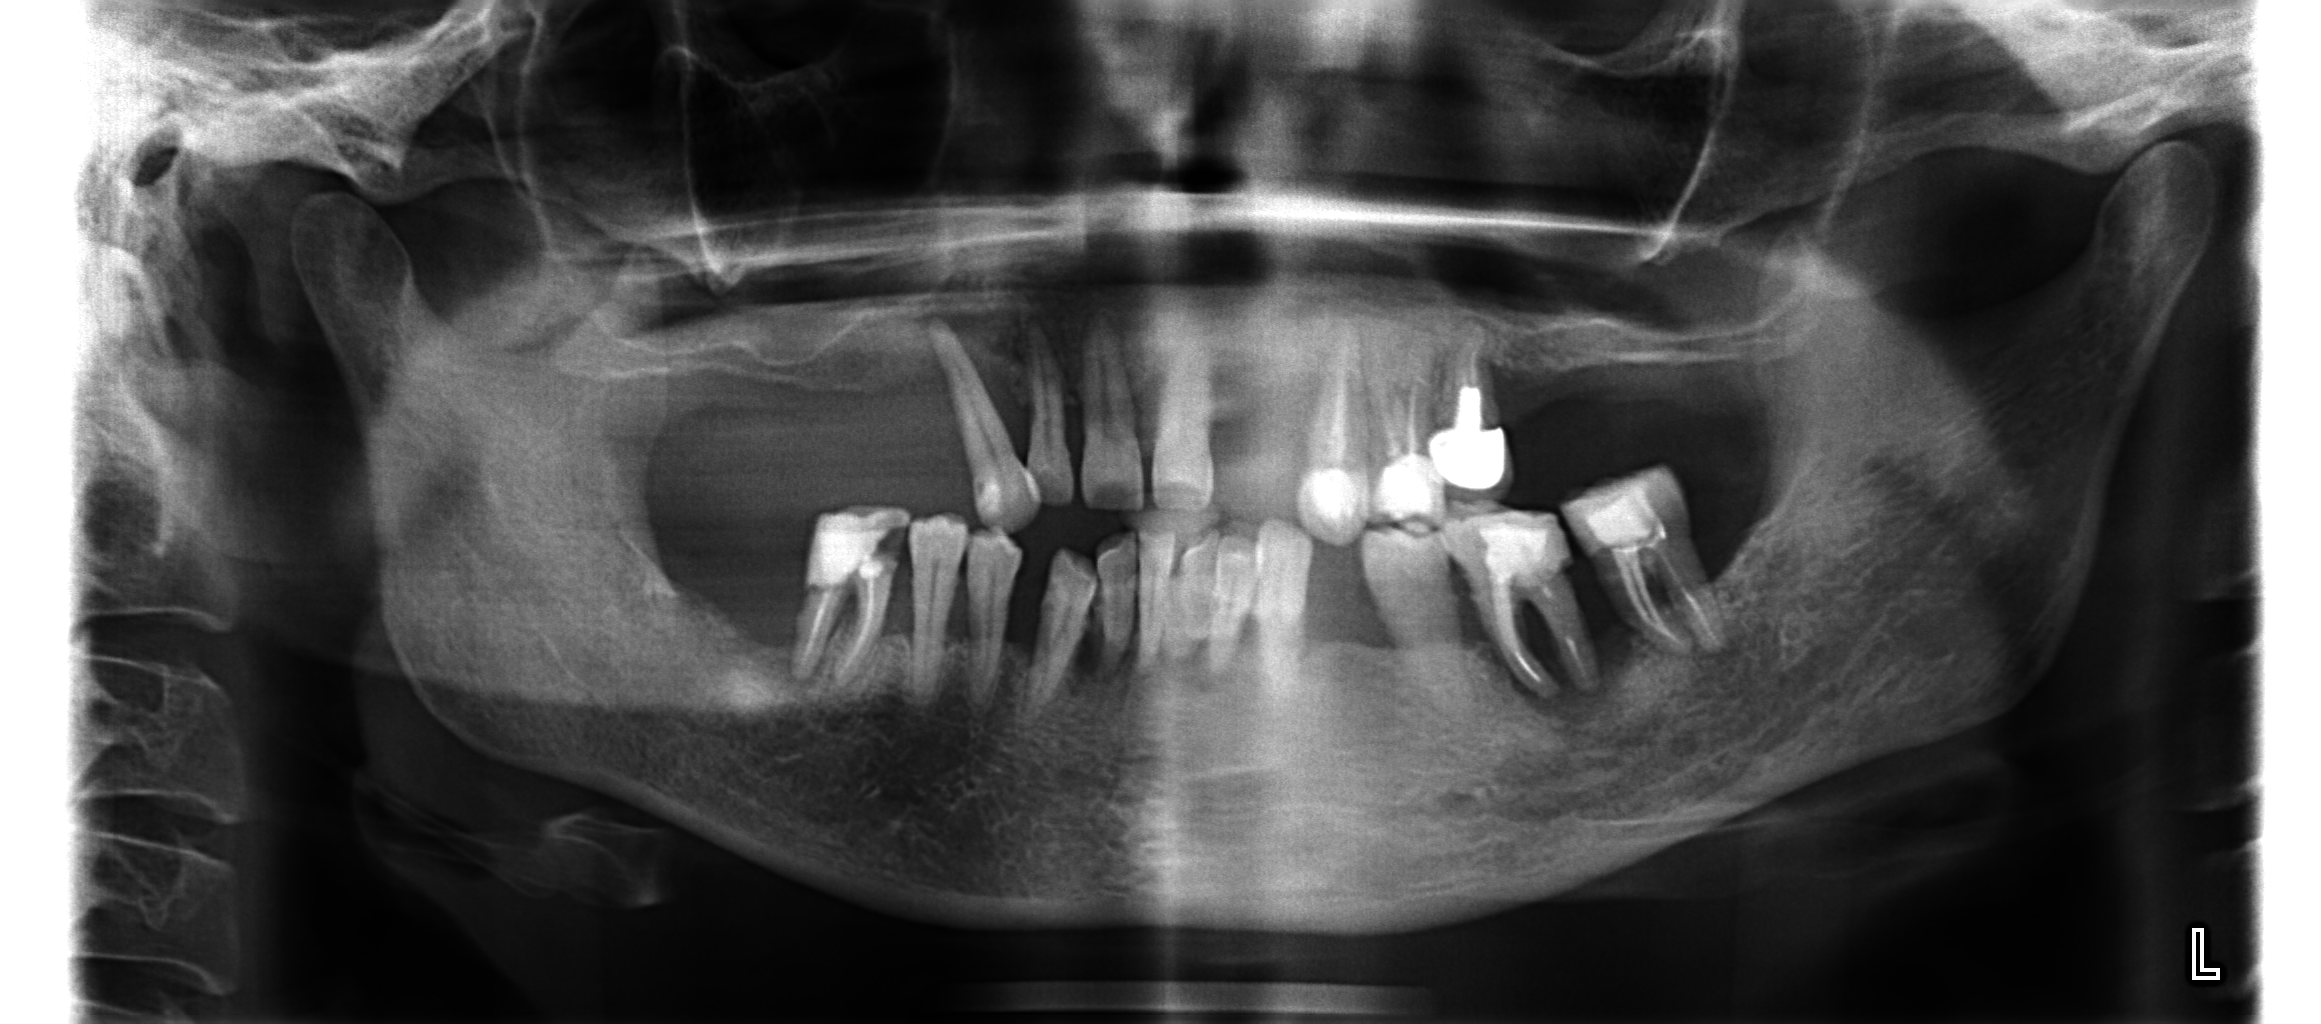

Задание оптг